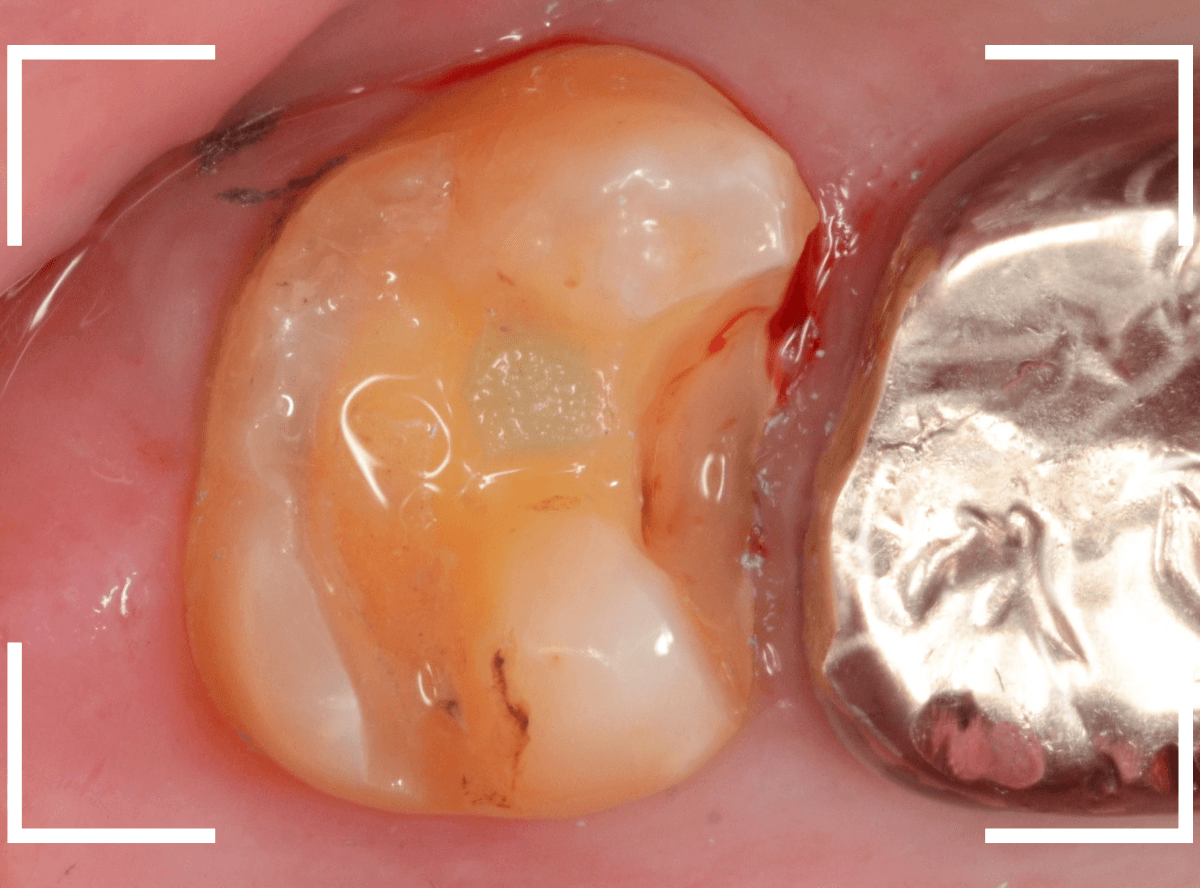

Case.24 レジンの下で虫歯が進行

上の奥歯の虫歯が見つかった患者さんです。

初診のチェックの際に、上から目視すると、レジンがつめてある〇部分が薄暗く黒くなっているので、これは虫歯があるな、とわかりました。

レントゲン写真で確認します。

赤いラインが虫歯と思われる部分、青いラインが歯の神経です。

先ほどの〇部分は明らかな虫歯になっているのがわかります。

この辺りはレジンがつめてありますが、その下もうっすらと虫歯になっていそうです。

治療を開始します。

先ほどの黒く見えた部分は少し削るとすぐに虫歯が出てきました。

手前の歯まで虫歯を除去した時点で、う蝕検知液で確認します。

赤く染色されている部分が虫歯です。

思ったよりも深めの虫歯ですね。

レジンを除去して虫歯をすべて治療したところです。

レジンの中も全体にうっすらと虫歯になっていました。

このくらいの虫歯でも、患者さんは自覚症状はありませんでした。

ご自身の自覚症状だけでは、虫歯の状況がわからないですし、自然に虫歯が治る事もありません。

いつものお話ですが、定期的なメンテナンスで、虫歯の早期発見・治療を心がけましょう。